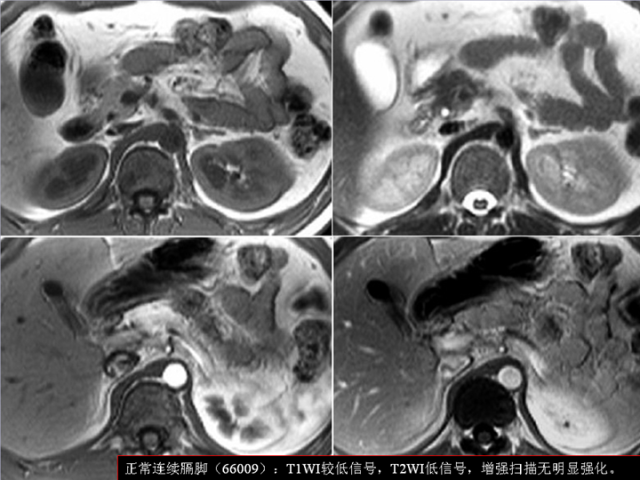

膈肌角解剖及常见变异

作者:王俭 上海长征医院